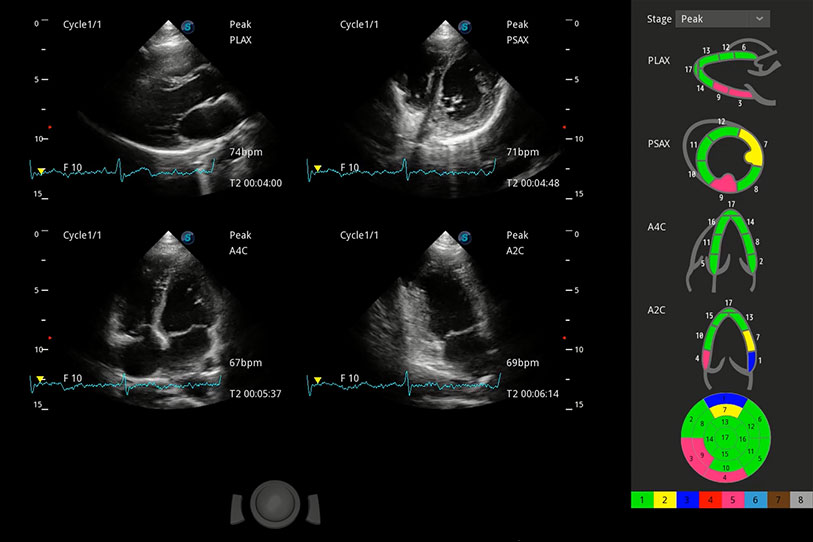

具备多种协议可选,同时支持17阶段划分法和专业的SE报告。

通过360度任意调节3条M型取样线,在同一心动周期上观察心脏不同位置的运动曲线,得到准确的心功能测量数据,有效评估心肌运动及左心室功能。